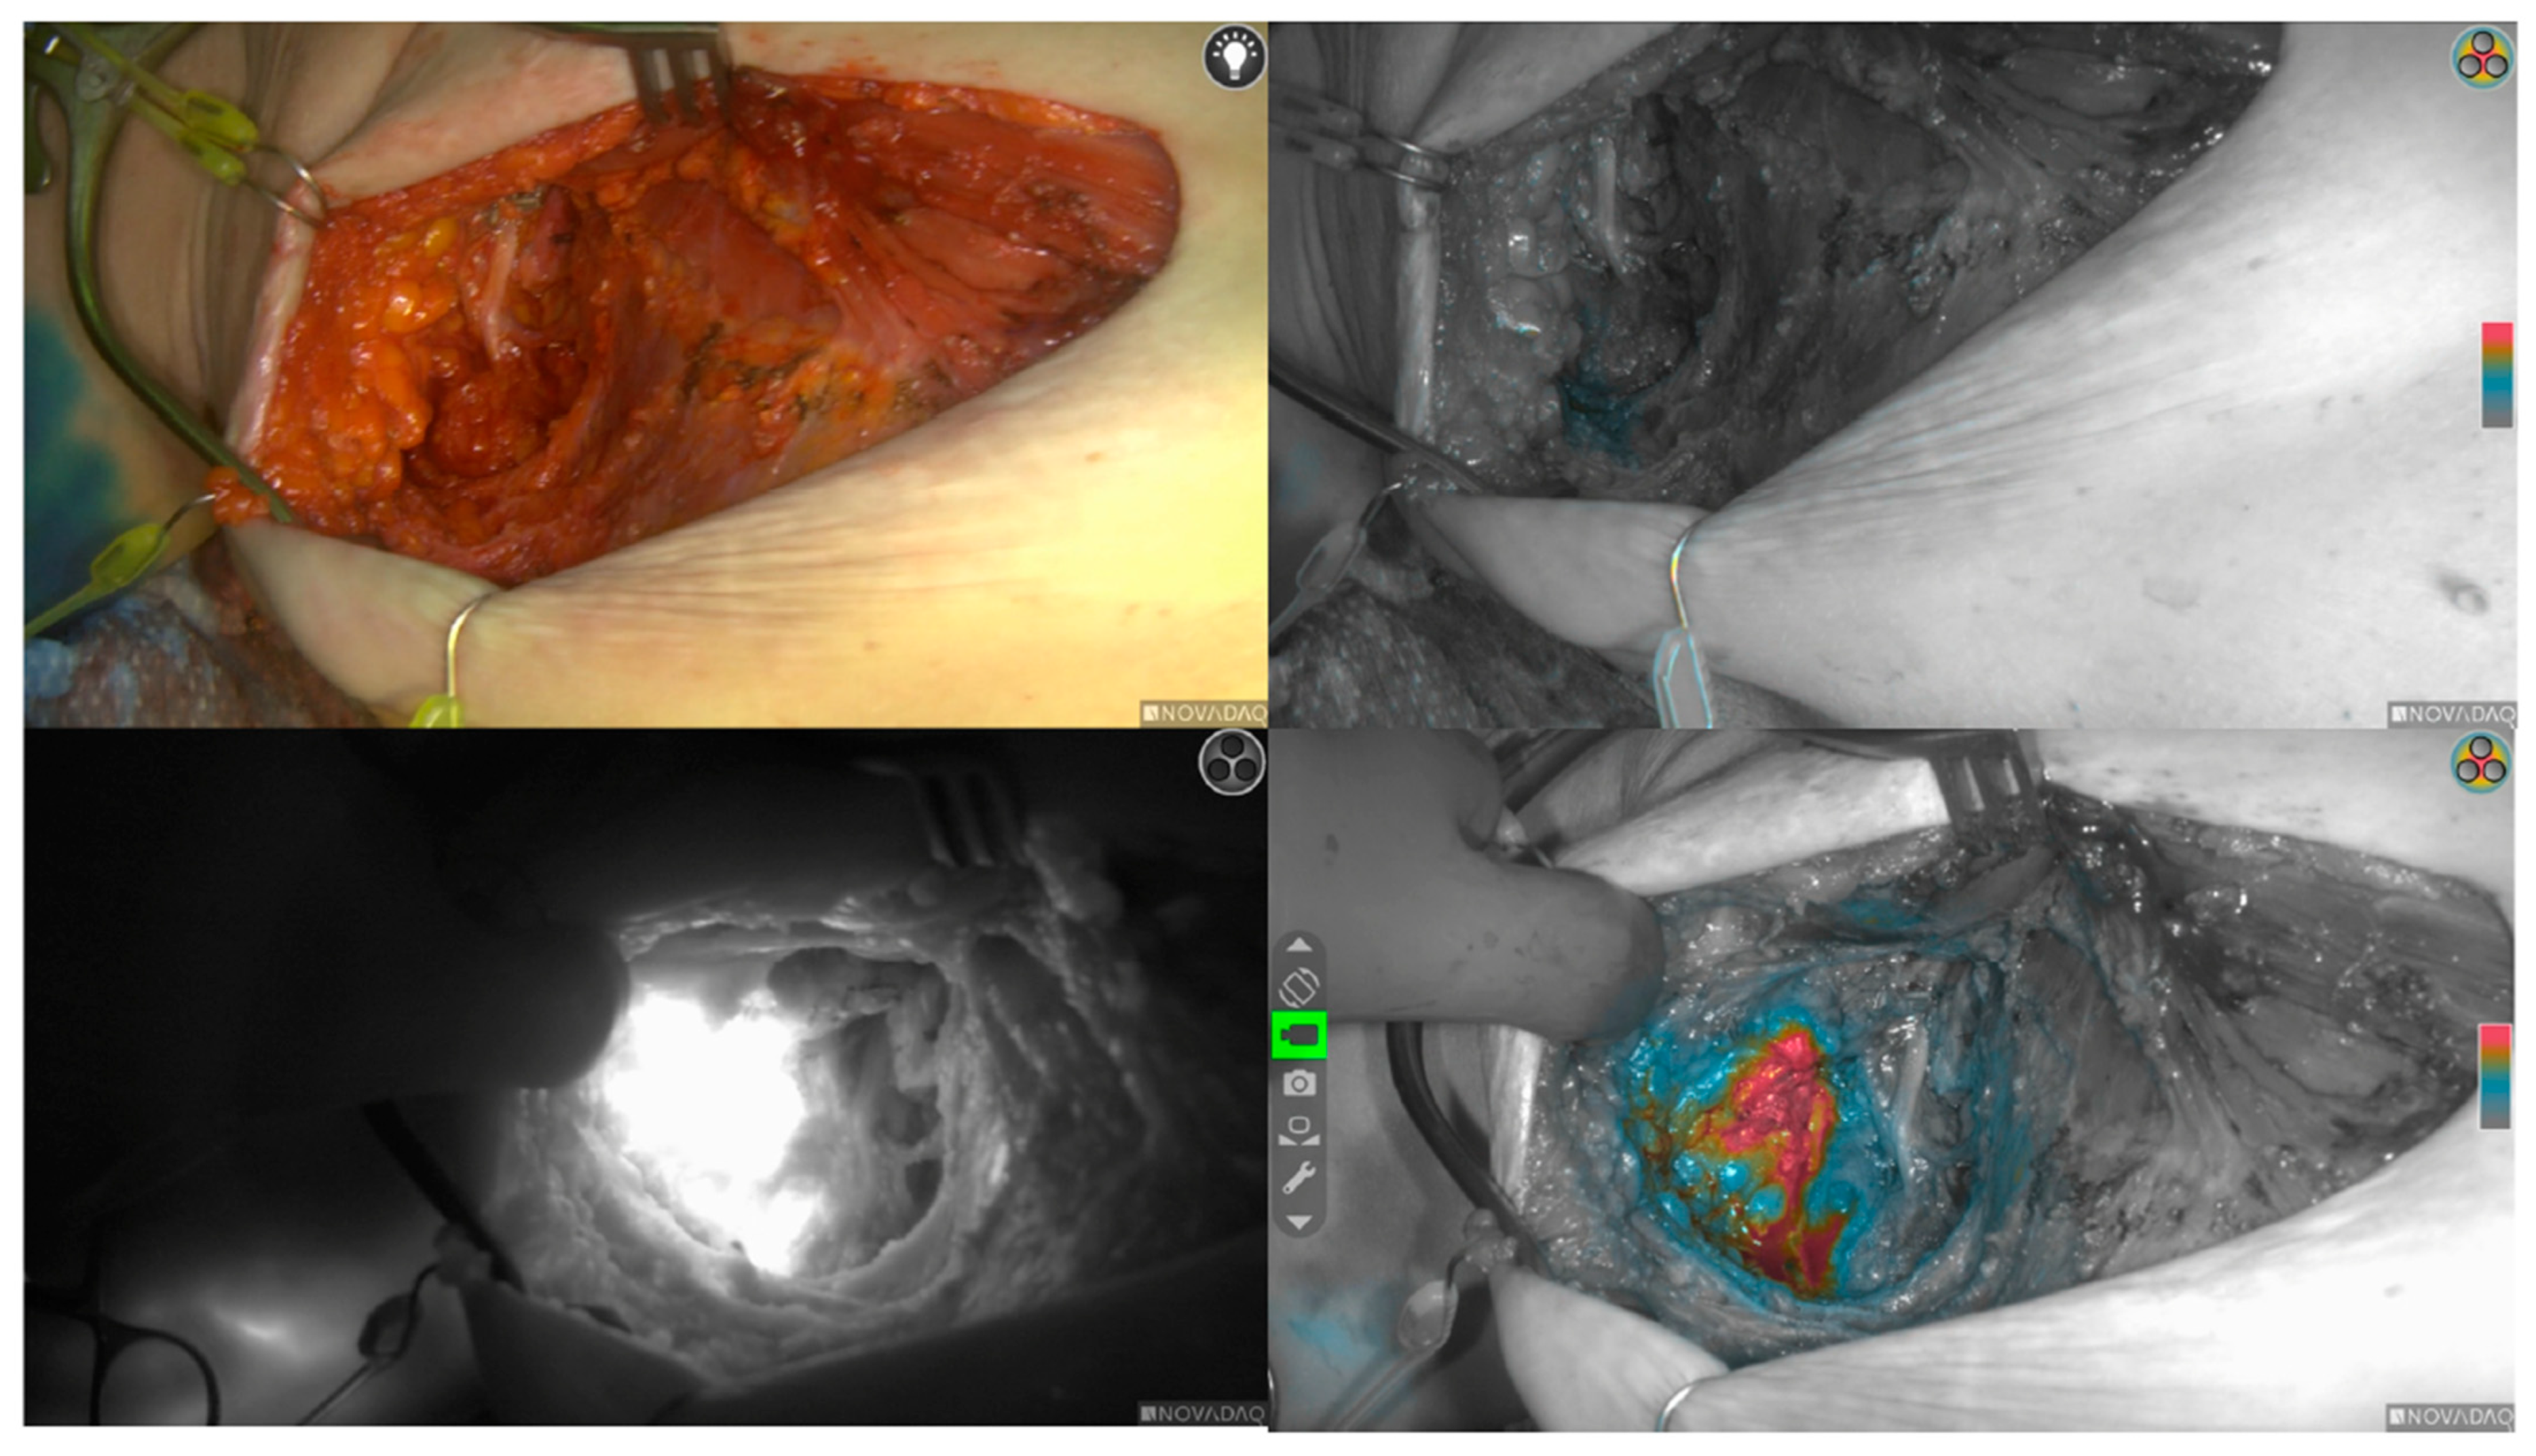

Figure 2. Right axillary lymph node dissection with ICG fluorescence and ISB guided axillary reverse mapping. Top left image: Right axillary lymph node dissection. Top right image: White light image displayed in greyscale with fluorescence overlaid in color scale. Bottom right image: ARM nodes observed in “color segmented fluorescence mode.” Increasing intensities of fluorescence transition from blue to yellow to red. Bottom left image: ARM nodes observed in “fluorescence mode.” Fluorescence image displayed in greyscale, providing the highest level of contrast between fluoresced and non-fluoresced tissue. ARM: axillary reverse mapping, ISB: isosulfan blue.

This retrospective review of a dual-dye axillary reverse mapping (ARM) technique during axillary lymph node dissection (ALND)—using indocyanine green (ICG) and isosulfan blue (ISB)—demonstrated marked differences in lymphatic channel identification by dye. Among 51 patients undergoing immediate lymphatic reconstruction (ILR), ICG fluorescence yielded a high ARM channel detection rate (86%), whereas ISB identified channels in 25% (Figure 2). Concurrent visualization with both tracers occurred in only 11.7% of channels. Overall, stained lymphatics were seen in 50 of 51 patients (98%); only one patient had no axillary visualization.

Following completion of ALND, transected lymphatics and adjacent axillary vein branches amenable to LVB were explored at the same incision site as the axillary dissection, using an operating microscope. ARM lymphatics were visualized as either blue lymphatics or fluorescent during exploration by detecting “hot spots” of leakage, using a near-infrared imaging system (SPY-PHI, Stryker Corporation, Kalamazoo, MI, USA) (Figure 4). LVB was performed by the senior author (D.L.C.) using a surgical microscope (Pentero 800, Carl Zeiss AG, Oberkochen, Germany) with 10-0 nylon sutures (Ethicon, Somerville, NJ, USA) in either an end-to-end or arborized fashion. Intraoperative number, location, and diameter measurements were recorded for all visualized lymphatic vessels stained with either blue dye alone, ICG, or both.